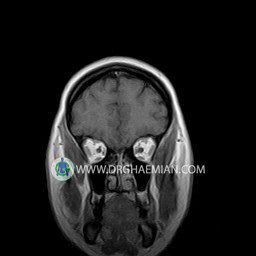

پزشکان اغلب از تصویربرداری ام آر آی برای تشخیص و درمان عارضه های پزشکی که فقط با استفاده از اشعه ایکس یا میدان مغناطیسی و امواج رادیویی قابل مشاهده است، استفاده می کنند. دستگاه ام آر آی تصاویر دقیق از ساختار های داخلی بدن ایجاد می کند. در این کیس نوریت اوربیت چب و سلای خالی بیمار مشاهده می شود.

ORBIT MRI

(with and without contrast)

Technique:Axial T1 , Axial , sagittal , coronal FSE T2 , coronal T1, sagittal fat sat T2 , Axial , sagittal T1 post Gd .

The both orbit are symmetrical and of normal size , with normal development of the orbital cones .

The bony orbital walls show a normal configuration with smooth and, sharp margins .

No foci of bone destruction , no circumscribed expansion of the bony or soft – tissue components of the orbital are evident .

The globes are symmetrical and of normal size and the ocular contents show normal signal characteristics .

The ocular walls are smooth , sharply defined , and of normal thickness .

The retrobulbar fat, ophthalmic vein and lacrimal apparatus are unremarkable .

Evaluable portions of the neurocranium and paranasal sinuses show no abnormalities .

No seen any evidence of ocular herniation

– Small fluid around the left optic nerve with mild edema suggestive for left optic neuritis

– Extension of suprasella cistern to sella with thin pituitary gland in floor of sella ( empty sella )

are seen

REPORTED BY :Dr DrNaser. Ghaemian.